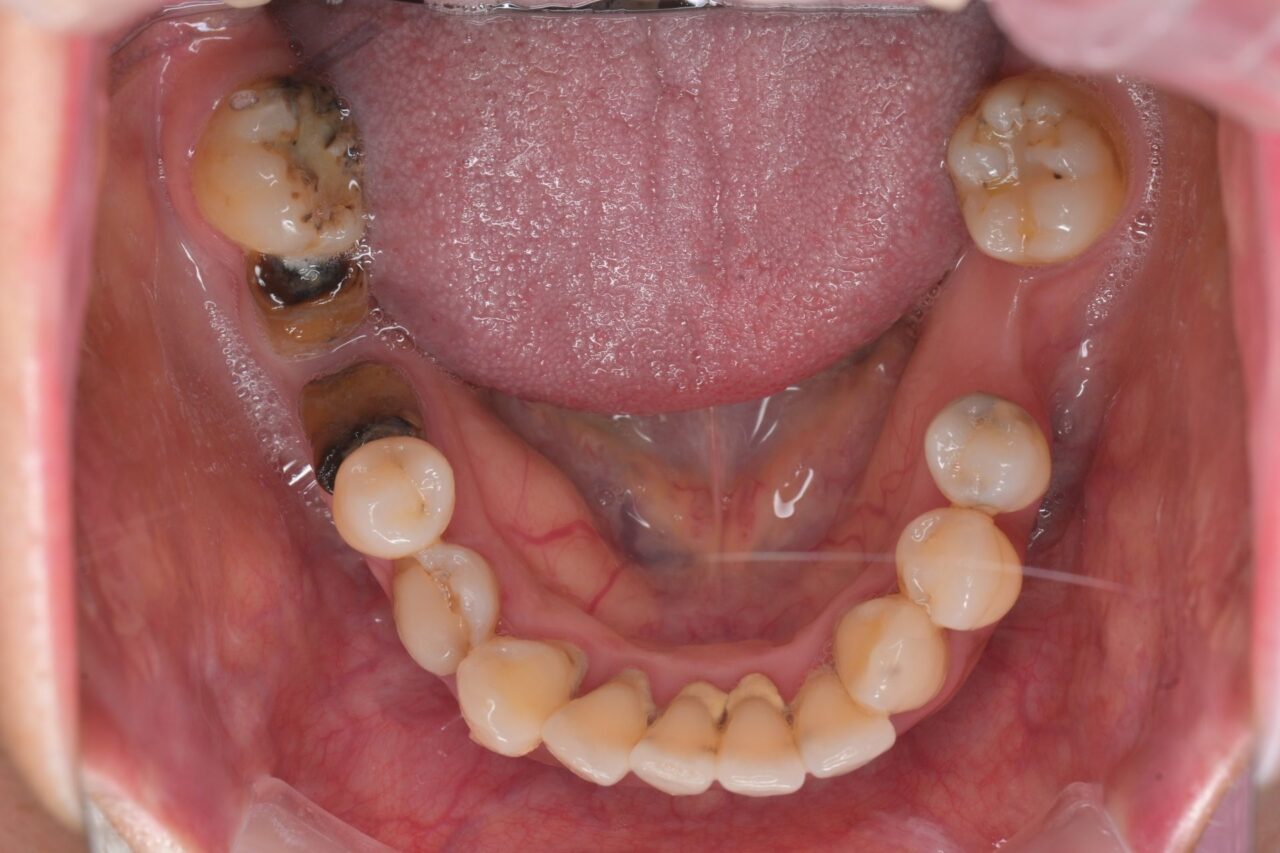

下面

歯石がたくさんついています。歯周病治療も同時に進めていきます。

親知らずも残っているので、即抜歯です。

※びわ湖大津デンタルクリニックでは、不要な親知らずは抜歯します。